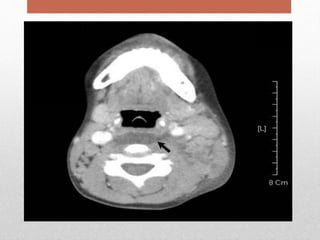

• Computed tomography (CT) is the imaging

modality of choice for retropharyngeal abscess.

• lateral neck radiograph may show an

increase in width of the soft tissues anterior to the

vertebrae.

Diagnosis • The laboratoryevaluation is non-specifi with leukocytosis. • contents of the abscess should be cultured • Computed tomography (CT) is the imaging modality of choice for retropharyngeal abscess. • lateral neck radiograph may show an increase in width of the soft tissues anterior to the vertebrae.